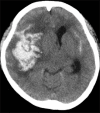

We report a case of a ruptured mycotic cerebral aneurysm caused by Nocardia infection. A 22-year-old immunocompromised woman with adult-onset Still's disease developed a subarachnoid hemorrhage (SAH). Digital subtraction angiography revealed a small aneurysm at the M2-3 bifurcation of the right middle cerebral artery. Cardiac ultrasonography showed vegetation at the posterior cardiac wall, suspecting infective endocarditis (IE). Gram-positive filamentous bacteria were observed in the necrotic tissue surrounding the aneurysm obtained during trapping surgery. Long-term blood culture showed that the cause of her cerebral mycotic aneurysm was nocardiosis. A mycotic ruptured cerebral aneurysm is an important cause of SAH in immunocompromised patients. Early diagnosis of IE, detection of gram-positive rods by Gram staining, and long-term culture to identify the bacteria is crucial in diagnosing nocardiosis.